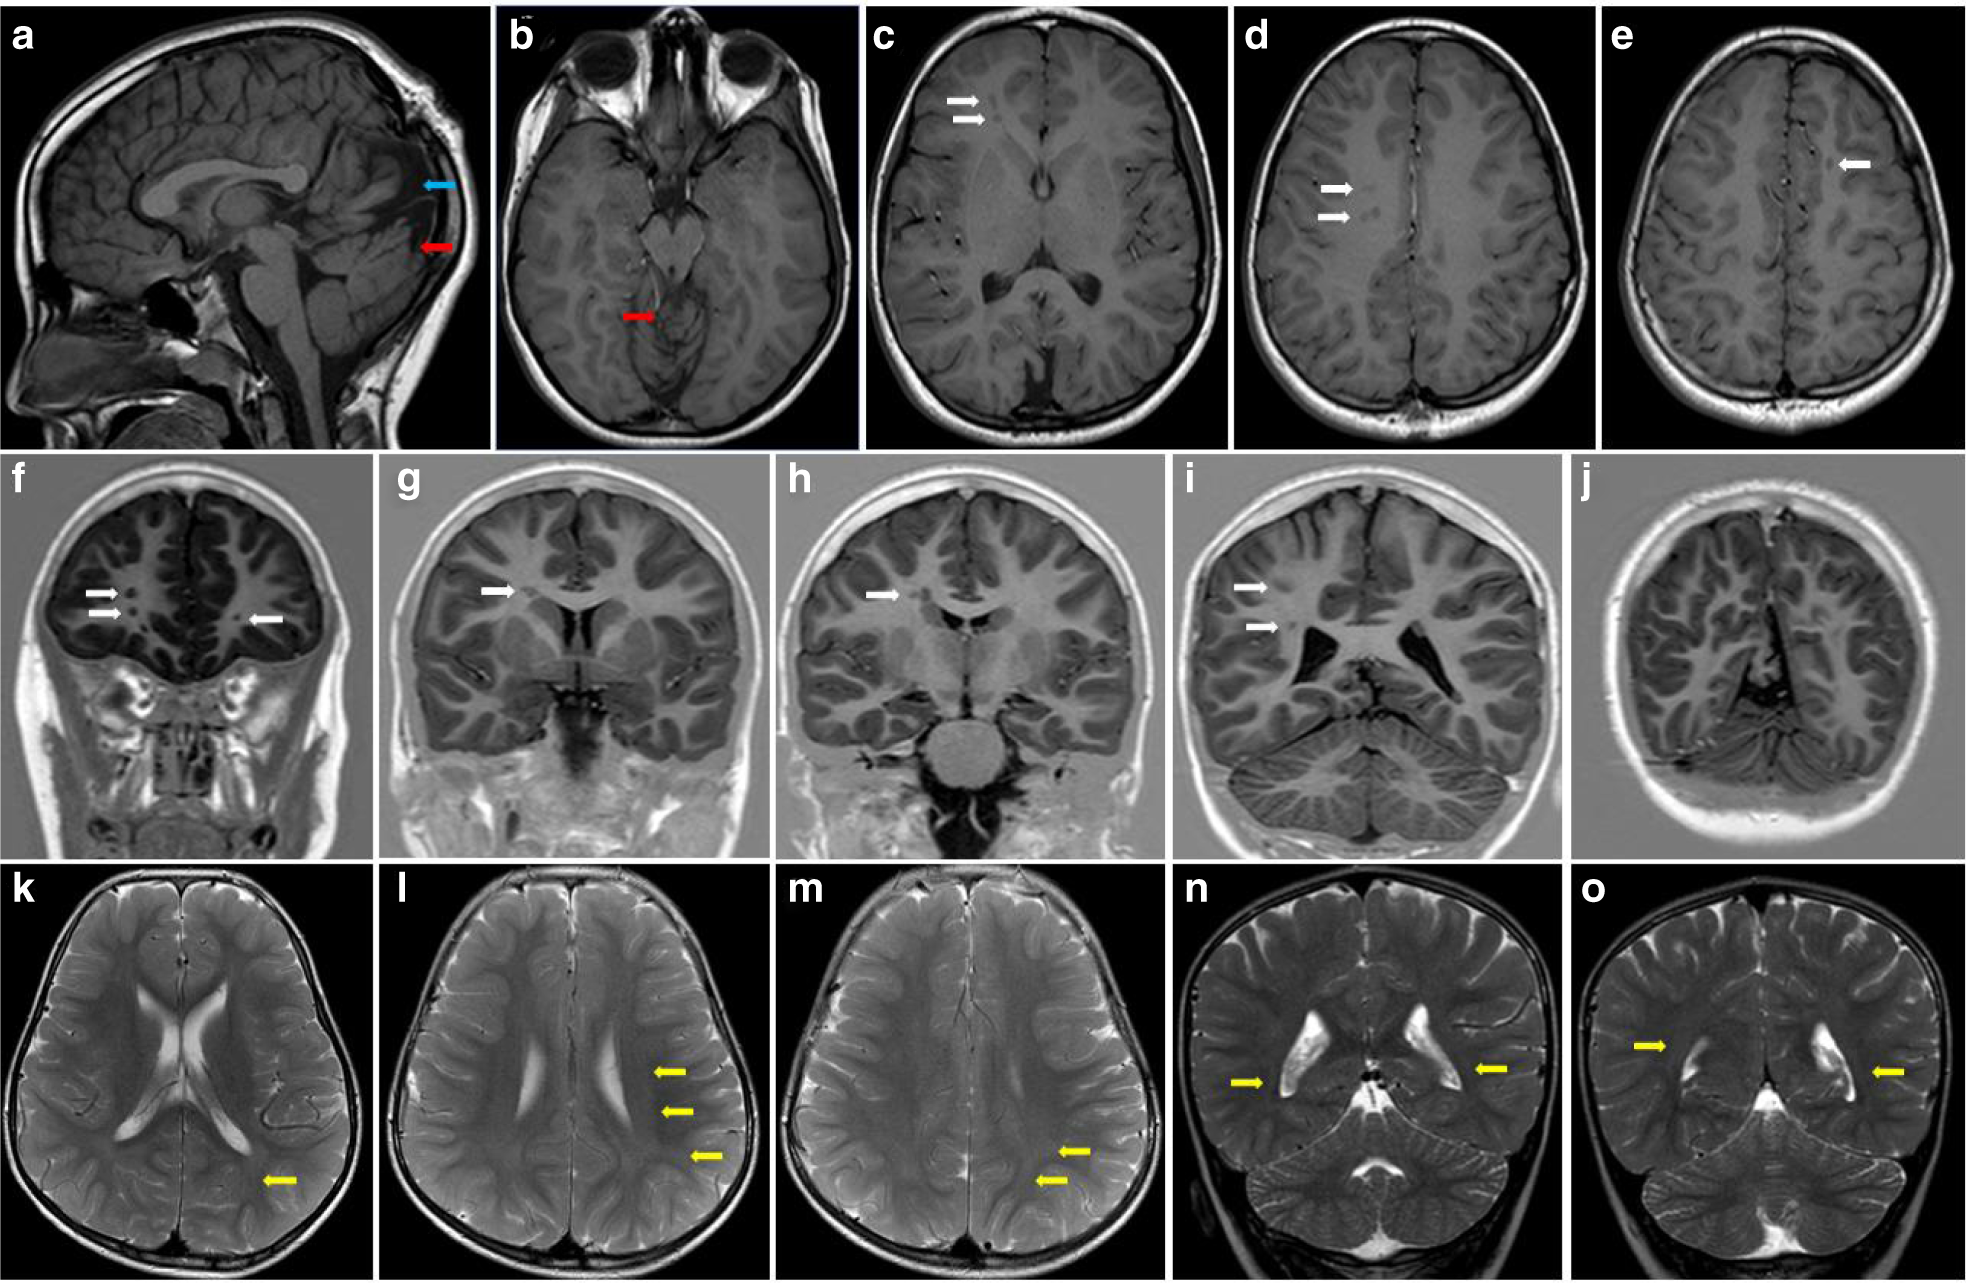

Fig. 3: Brain magnetic resonance image (MRI) affected individuals carrying expected-pathogenic variants in ARFGEF1.

Brain MRI of individual 3 carrying the NM_006421.4:c.3592-2A>G variant (a–j), and of individual 2 carrying the p.(Arg1774*) variant (k–o). T1-weighted sagittal (a), axial T1 (b–e) and T2 fluid-attenuated inversion recovery (FLAIR) (k–m), and coronal (f–I and n–o) brain imaging. Note the nodular periventricular heterotopia (white arrows), occipital meningocele (blue arrow), and disrupted cerebellar vermis (red arrows) for patient 3 and the bilateral and diffuse signal hyperintensities of the subcortical white matter, especially of the posterior regions (yellow arrows) for individual 2.